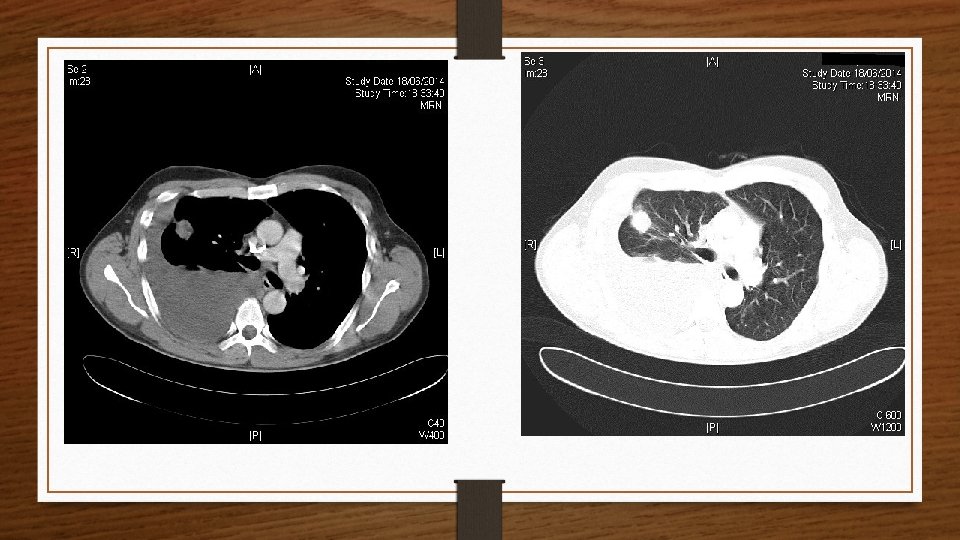

Radiografía de Tórax

TC TÓRAX

RESUMEN • Paciente varón de 50 años fumador • Dolor torácico de características pleuríticas y disnea • Exploración: hipofonesis + abolición mv • Rx + TC: Derrame pleural derecho